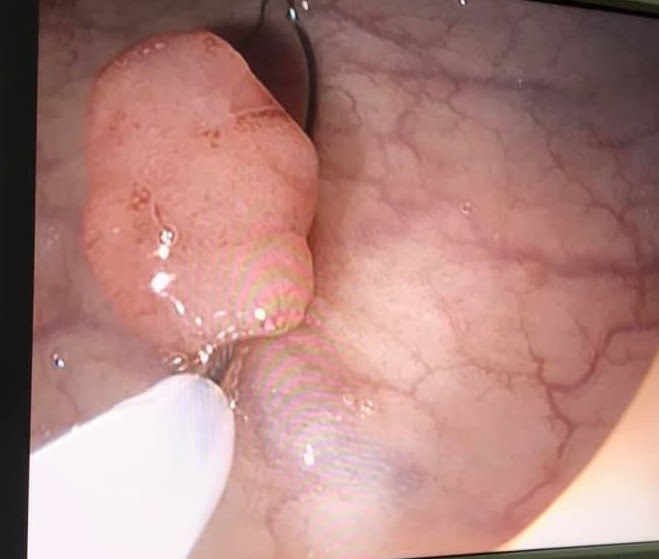

Ngày 05/11/2020, Trung tâm Y tế TP Móng Cái tiếp nhận bệnh nhân đến nội soi đại tràng toàn bộ tại Phòng Nội soi tiêu hóa- Nội soi can thiệp TTYT TP Móng Cái. Bệnh nhân được chẩn đoán có 1 Polyp KT ~ 0.8 cm, được tiến hành cắt qua nội soi thành công. Sau cắt BN tỉnh, không đau bụng, chân cắt không chảy máu, được tư vấn về chế độ ăn, sinh hoạt và theo dõi sau cắt polyp. Bệnh nhân được ra viện ngay sau cắt polyp.

Kĩ thuật được thực hiện bởi Thạc sỹ- Bác sỹ Đoàn Ngọc Thuỷ- GĐ Trung tâm.